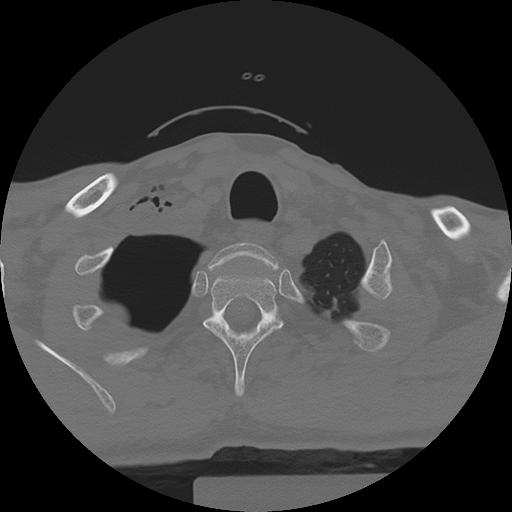

11 HUESO,,Axial,2.0,HUESO,,